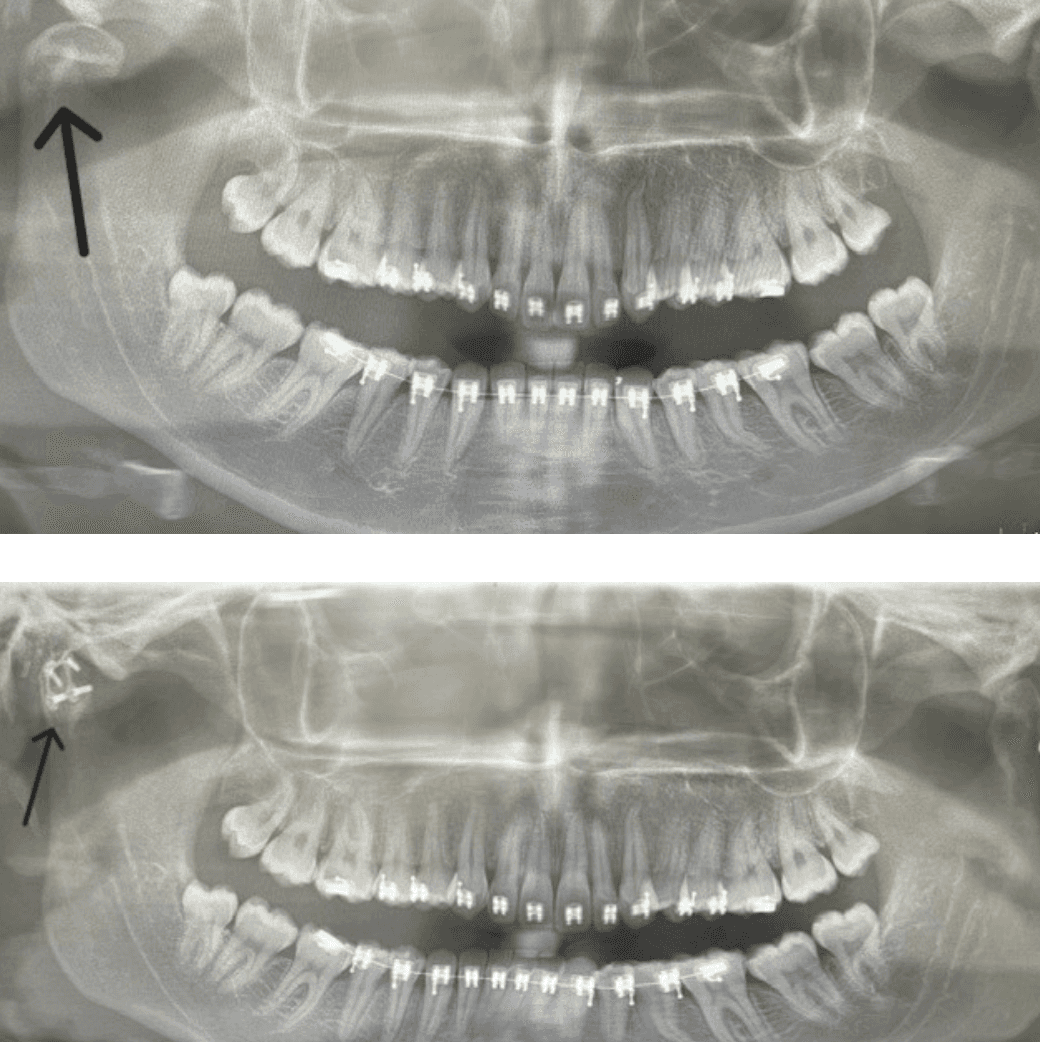

Surgery involves repairing injuries to the face, jaw and neck, addressing damage to soft tissues and bones in order to restore function, improve appearance and address psychological impacts. (Condilar fracture vs Repair of fracture)